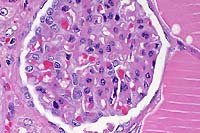

- Case 8-3 . Kidney. The glomerulus contains increased

numbers of mesangial cells which compress glomerular capillaries.

Adjacent tubules are filled with eosinophilic material forming

- 1. Kidney: Tubular epithelial degeneration and necrosis,

multifocal, mild to moderate, with intratubular proteinaceous

casts and erythrocytic debris, and intraerythrocytic piroplasms,

baboon (Papio cynocephalus/anubis), nonhuman primate.

3. Kidney: Glomerulopathy, membranous, global, multifocal, mild

to moderate.

glomeruli are hypercellular and contain increased amounts of

mesangial matrix; global and segmental synechiae are present

- Multifocally, some kidney tubules are filled by an eosinophilic

homogenous material interpreted as proteinaceous fluid, while

a few tubules contain fibrin and sloughed epithelial cells. Still

other tubules contain moderate amounts of a more brightly eosinophilic,

globular to crystalline material interpreted to be hemoglobin.

Protein droplets occur within tubular epithelial cells, especially

within proximal convoluted tubules. Histochemical stains performed

at the AFIP demonstrate abundant iron within tubules and in tubular

epithelial cells.